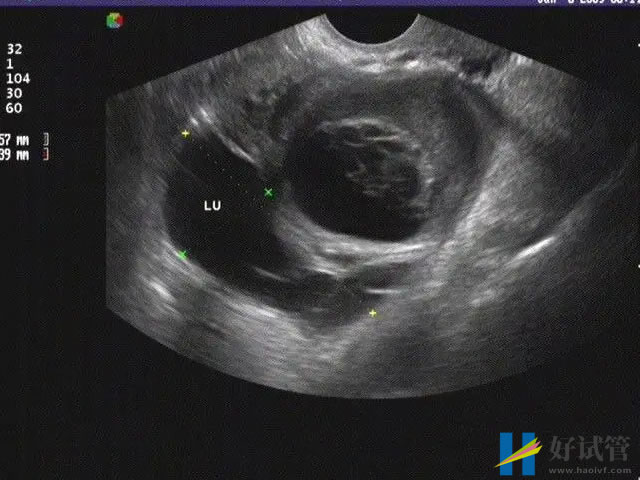

- 输卵管闭塞不通:大概率是因为结核、附件炎、宫外孕、输卵管结扎等因素导致的,一般通过腹腔镜或宫腔镜检查可以直观的判断,可以采用西医以导丝复通术为主进行治疗;